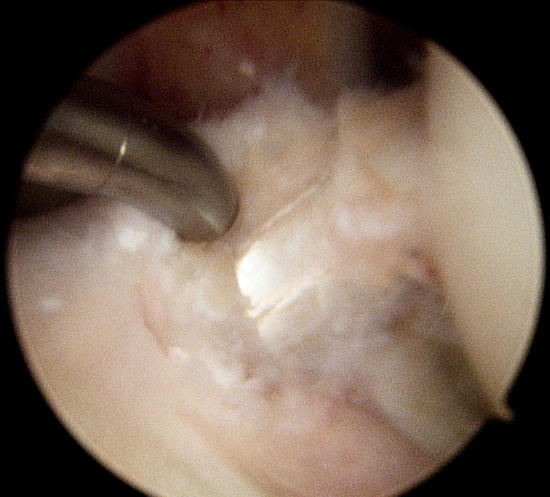

Artroskopik cerrahi nedir

Artroskopi, bir santimetrelik küçük kesiler kullanılarak, eklemlerin içinin kalem boyunda bir kamera ile görüntülenmesidir. Yetmişli yıllarda sadece teşhis amaçlı kullanılırken, günümüzde gelişen teknoloji ve özel aletler sayesinde hem teşhis hem tedavi için kullanılmaktadır. En sık diz eklemi olmak üzere, omuz, ayak bileği, el bileği, dirsek ve kalça eklemini ilgilendiren hastalıkların tedavisinde yaygın kullanım alanı bulmuştur.